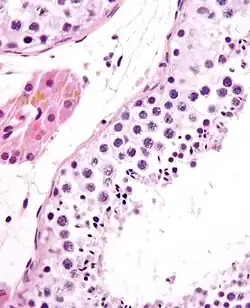

![]() A mature human Spermatozoon | |

Spermatogenesis is the process by which haploid spermatozoa develop from germ cells in the seminiferous tubules of the testicle. This process starts with the mitotic division of the stem cells located close to the basement membrane of the tubules.[1] These cells are called spermatogonial stem cells. The mitotic division of these produces two types of cells. Type A cells replenish the stem cells, and type B cells differentiate into primary spermatocytes. The primary spermatocyte divides meiotically (Meiosis I) into two secondary spermatocytes; each secondary spermatocyte divides into two equal haploid spermatids by Meiosis II. The spermatids are transformed into spermatozoa (sperm) by the process of spermiogenesis. These develop into mature spermatozoa, also known as sperm cells.[2] Thus, the primary spermatocyte gives rise to two cells, the secondary spermatocytes, and the two secondary spermatocytes by their subdivision produce four spermatozoa and four haploid cells.[3]

Spermiogenesis

During spermiogenesis, the spermatids begin to form a tail by growing microtubules on one of the centrioles, which turns into basal body. These microtubules form an axoneme. Later the centriole is modified in the process of centrosome reduction.[16] The anterior part of the tail (called midpiece) thickens because mitochondria are arranged around the axoneme to ensure energy supply. Spermatid DNA also undergoes packaging, becoming highly condensed. The DNA is packaged firstly with specific nuclear basic proteins, which are subsequently replaced with protamines during spermatid elongation. The resultant tightly packed chromatin is transcriptionally inactive. The Golgi apparatus surrounds the now condensed nucleus, becoming the acrosome.

Maturation then takes place under the influence of testosterone, which removes the remaining unnecessary cytoplasm and organelles. The excess cytoplasm, known as residual bodies, is phagocytosed by surrounding Sertoli cells in the testes. The resulting spermatozoa are now mature but lack motility. The mature spermatozoa are released from the protective Sertoli cells into the lumen of the seminiferous tubule in a process called spermiation.